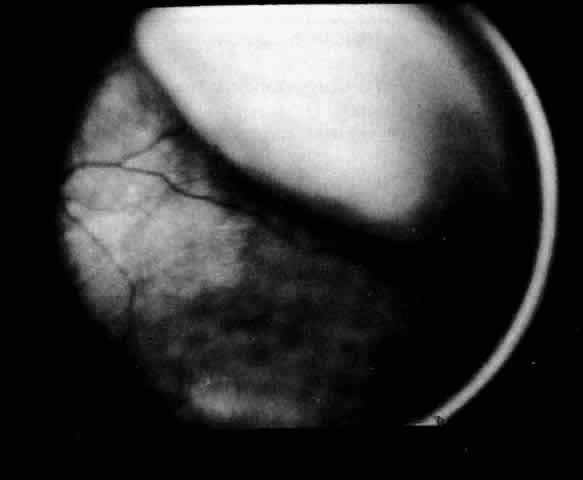

Ciliochoroidal effusions may have an annular, lobular (Fig. 4), or flat (Fig. 5) ophthalmoscopic appearance. Annular effusions occur around the ciliary body and peripheral choroid. Lobular effusions are large hemispheric detachments that bulge toward the center of the globe. Flat effusions are most often apparent in isolated peripheral choroidal areas, where local structures limit fluid extension. A local stimulus, such as a limbal incision, can lead to suprachoroidal edema, even in remote areas, by way of free dissection of fluid. Occasionally, patients will present with coexisting ciliochoroidal effusion and rhegmatogenous retinal detachment.23–25 The retinal hole may be hidden in the choroidal mounds. Such detachments tend to occur in older patients who have a history of previous ocular surgery.

Fig. 4. Clinical appearance of a lobular type of ciliochoroidal effusion.